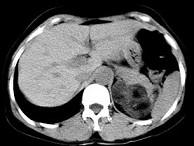

问题 男性,28岁,左腰背酸胀5个月,CT检查如图所示,应诊断为()

选项 A.左肾上腺髓样脂肪瘤 B.左肾上腺错构瘤 C.左肾上腺嗜铬细胞瘤 D.左肾上腺腺瘤 E.左肾上腺转移瘤

答案 B